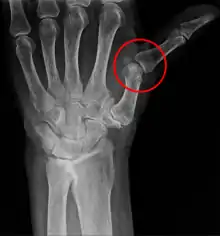

A subluxation is an incomplete or partial dislocation of a joint or organ.[1]

According to the World Health Organization (WHO), a subluxation is a "significant structural displacement", and is therefore always visible on static imaging studies, such as X-rays.[2][3][4]

A subluxation of a joint is where a connecting bone is partially out of the joint.[6] In contrast to a luxation, which is a complete separation of the joints, a subluxation often returns to its normal position without additional help from a health professional.[7] An example of a joint subluxation is a nursemaid's elbow, which is the subluxation of the head of the radius from the annular ligament. Other joints that are prone to subluxations are the shoulders, fingers, kneecaps, ribs, wrists, ankles, and hips affected by hip dysplasia. A spinal subluxation is visible on X-rays and can sometimes impinge on spinal nerve roots, causing symptoms in the areas served by those roots. In the spine, such a displacement may be caused by a fracture, spondylolisthesis, rheumatoid arthritis,[8] severe osteoarthritis, falls, accidents and other traumas. This is common in Ehlers–Danlos Syndrome.[9]